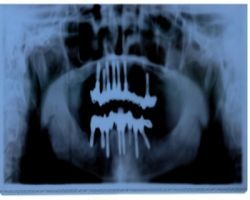

Auflagerungsplastik bedeutet, dass andernorts eine Knochenscheibe entnommen wird, die dann auf den zurück gegangenen eigenen Knochen im Bereich des Knochenfortsatzes aufgelagert wird. Die Fixation kann dann mit feinen Mikroschrauben oder aber mit Implantaten erfolgen. Der Knochen für diese Auflagerungsplastik kann an verschiedenen Entnahmestellen gewonnen werden, so z. B. am Beckenkamm, am Schienbein oder auch am Schädelknochen. Nachdem die letzte Entnahmestelle den meisten Patienten eher unsympathisch ist, hat sich der Beckenkamm als die am häufigsten genutzte Entnahmestelle, insbesondere für größere Knochenstücke durchgesetzt. Über einen Zugang im Bereich des Hüftknochens kann dann über einen ca. 2cm langen Schnitt ein ausreichendes Knochenstück entnommen werden. Dieses wird dann nach entsprechender Präparation und Bearbeitung als sog. mono- oder bikortikales Transplantat auf den Knochen aufgebracht. Wichtig ist es hierbei auf eine ausreichende Knochenanlagerungsfläche zu achten. Auch der ortständige Knochen muss angefrischt werden, um ein Verwachsen mit dem neuen Knochen zu ermöglichen. Danach können dann die Implantate eingebracht werden.